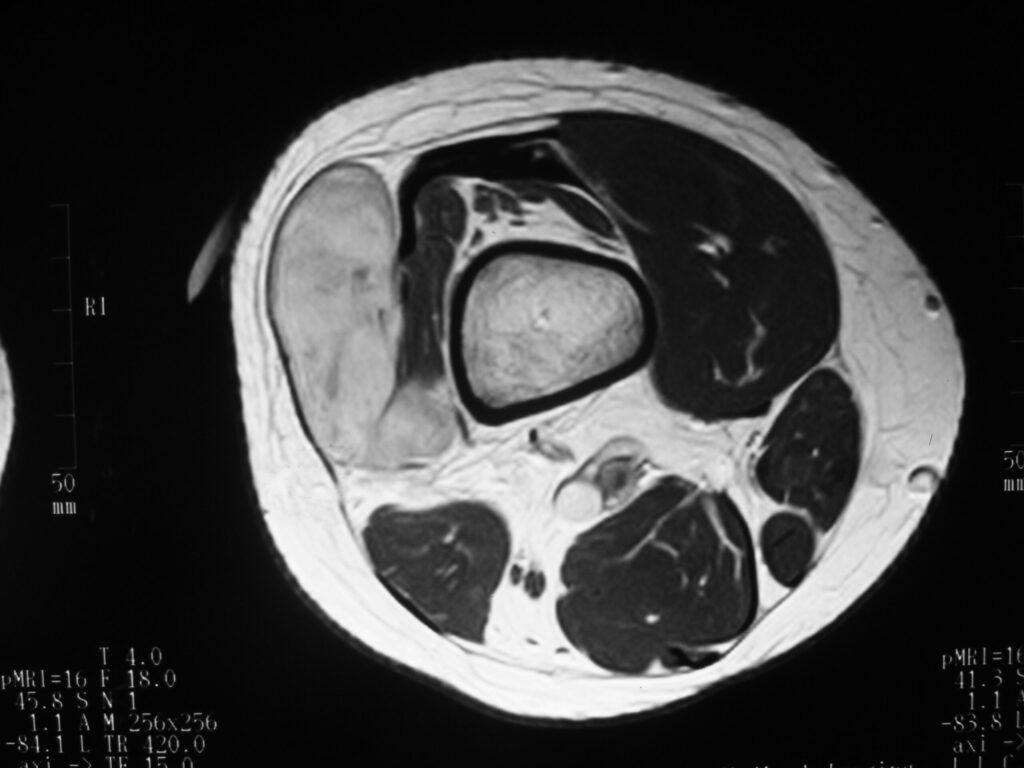

MRI

Shows multiloculated, heterogeneous mass.

“Triple Signal Intensity sign”; hypointense, isointense and hyperintense with fat on T2 – weighted MRI imaging. This sign is present in 30 to 50% of the cases. (Fig.3)

Under contrast enhancement Synovial Sarcoma appears heterogeneous and demonstrate areas of nodular enhancement.

In approximately 30% of cases a multiple vascular cannel may be identified

Synovial sarcomas may have a cystic appearance and are often mistaken for ganglion cysts especially those adjacent to tendons and in the foot and ankle.